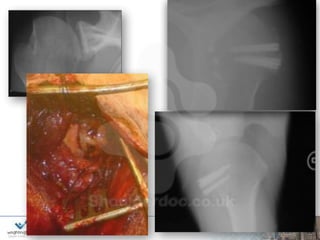

Pragmatic 2:

28yr male

Multiple recurrent traumatic dislocations with

reducing force.

Dislocating dressing & sleep

Now avoidance

Unable to work as nurse